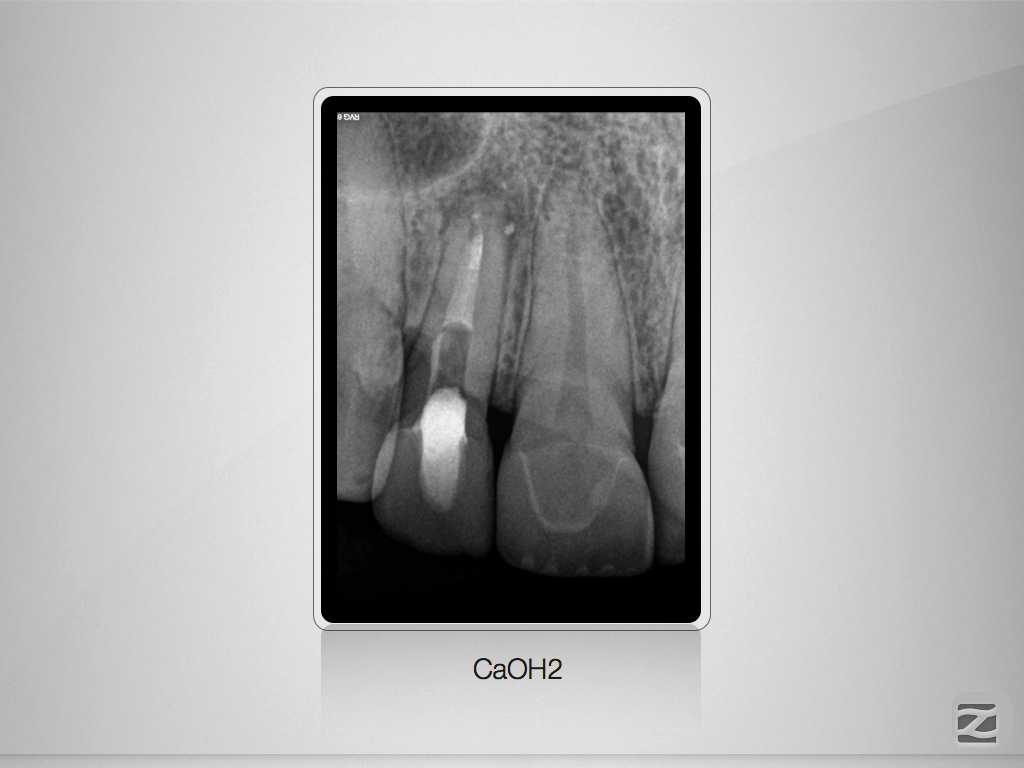

Kurioses Leakage